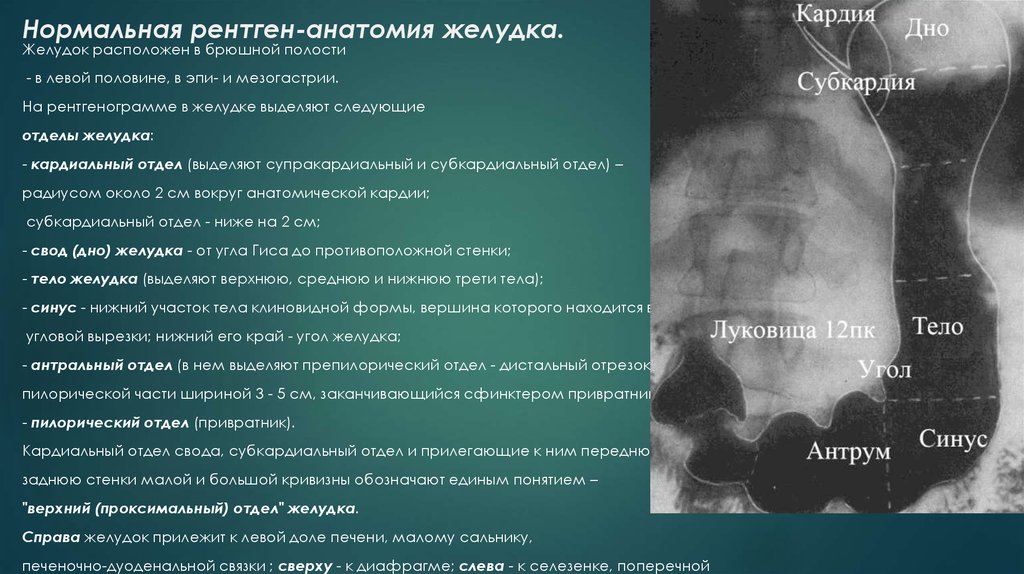

Современные технологии в медицине: рентгенодиагностика заболеваний желудка

Раздел: Фотогалерея мыслей